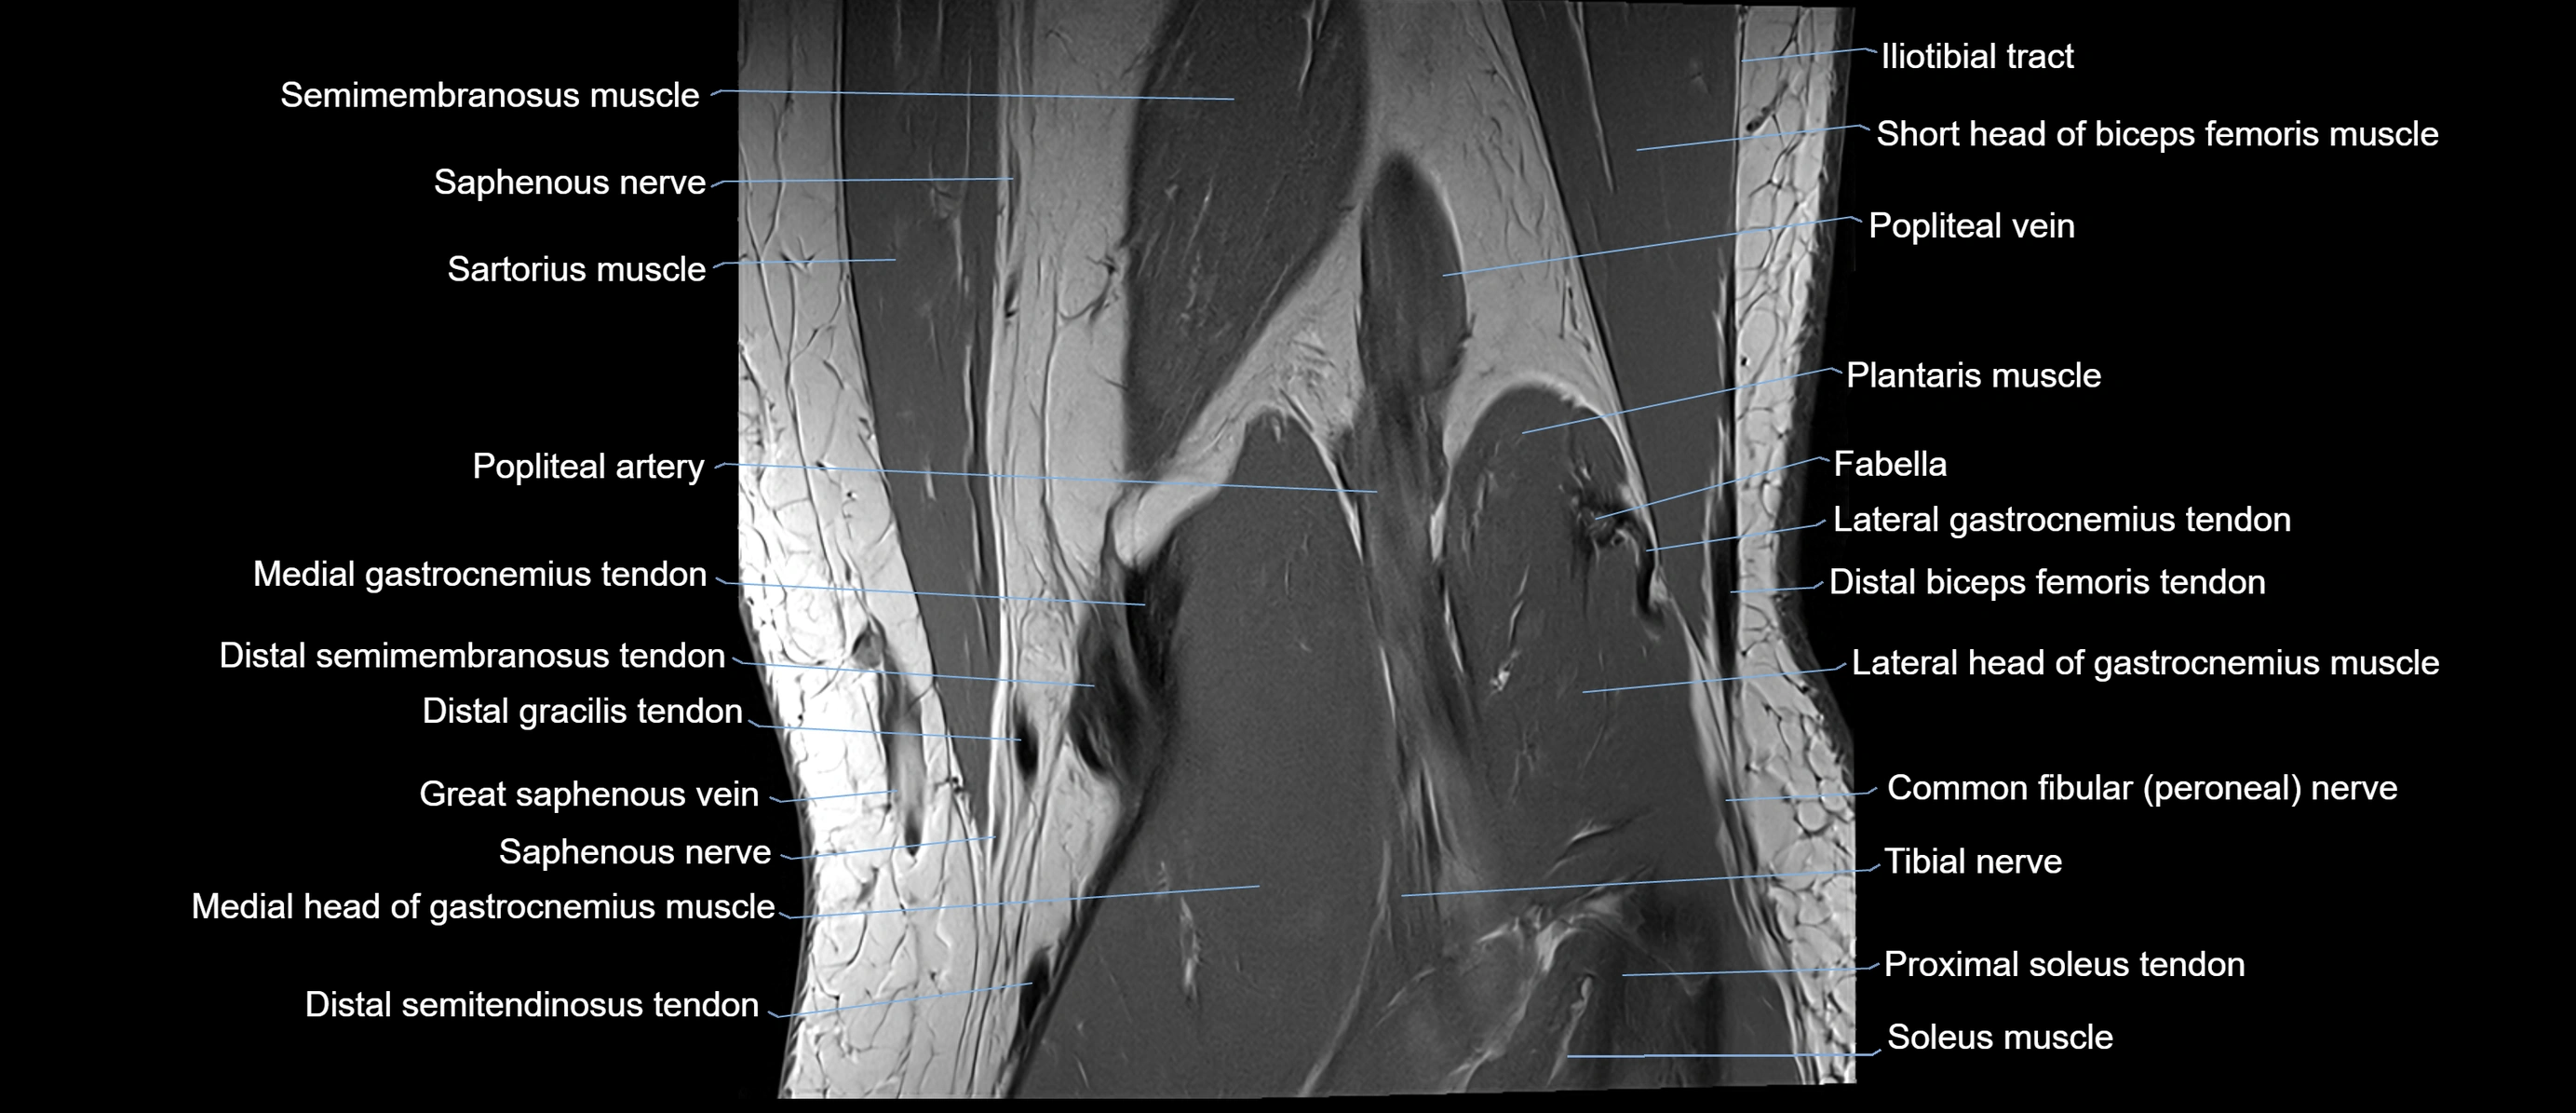

- Popliteal artery

- Popliteal vein

- Saphenous nerve

- Sartorius muscle

- Semimembranosus muscle

- Soleus muscle

- Tibial nerve